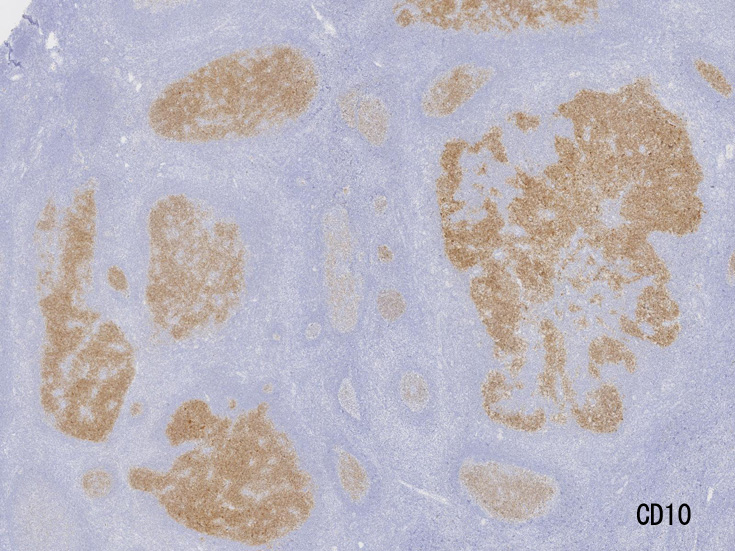

大きな胚中心を持つ多数のリンパ濾胞が見られる。胚中心の辺縁は不明瞭でマントル層も薄くなっている。1カ所マントル層リンパ球の侵入によりバラバラになった巨大な胚中心が認められ, macrofollicular patternと記載されるPTGCです。

鑑別にあがるfollicular lymphoma floral variantは全ての濾胞が腫瘍性であり, 本性例では除外可能と考える。

Diagnosis: Reactive lymphadenitis with PTGC